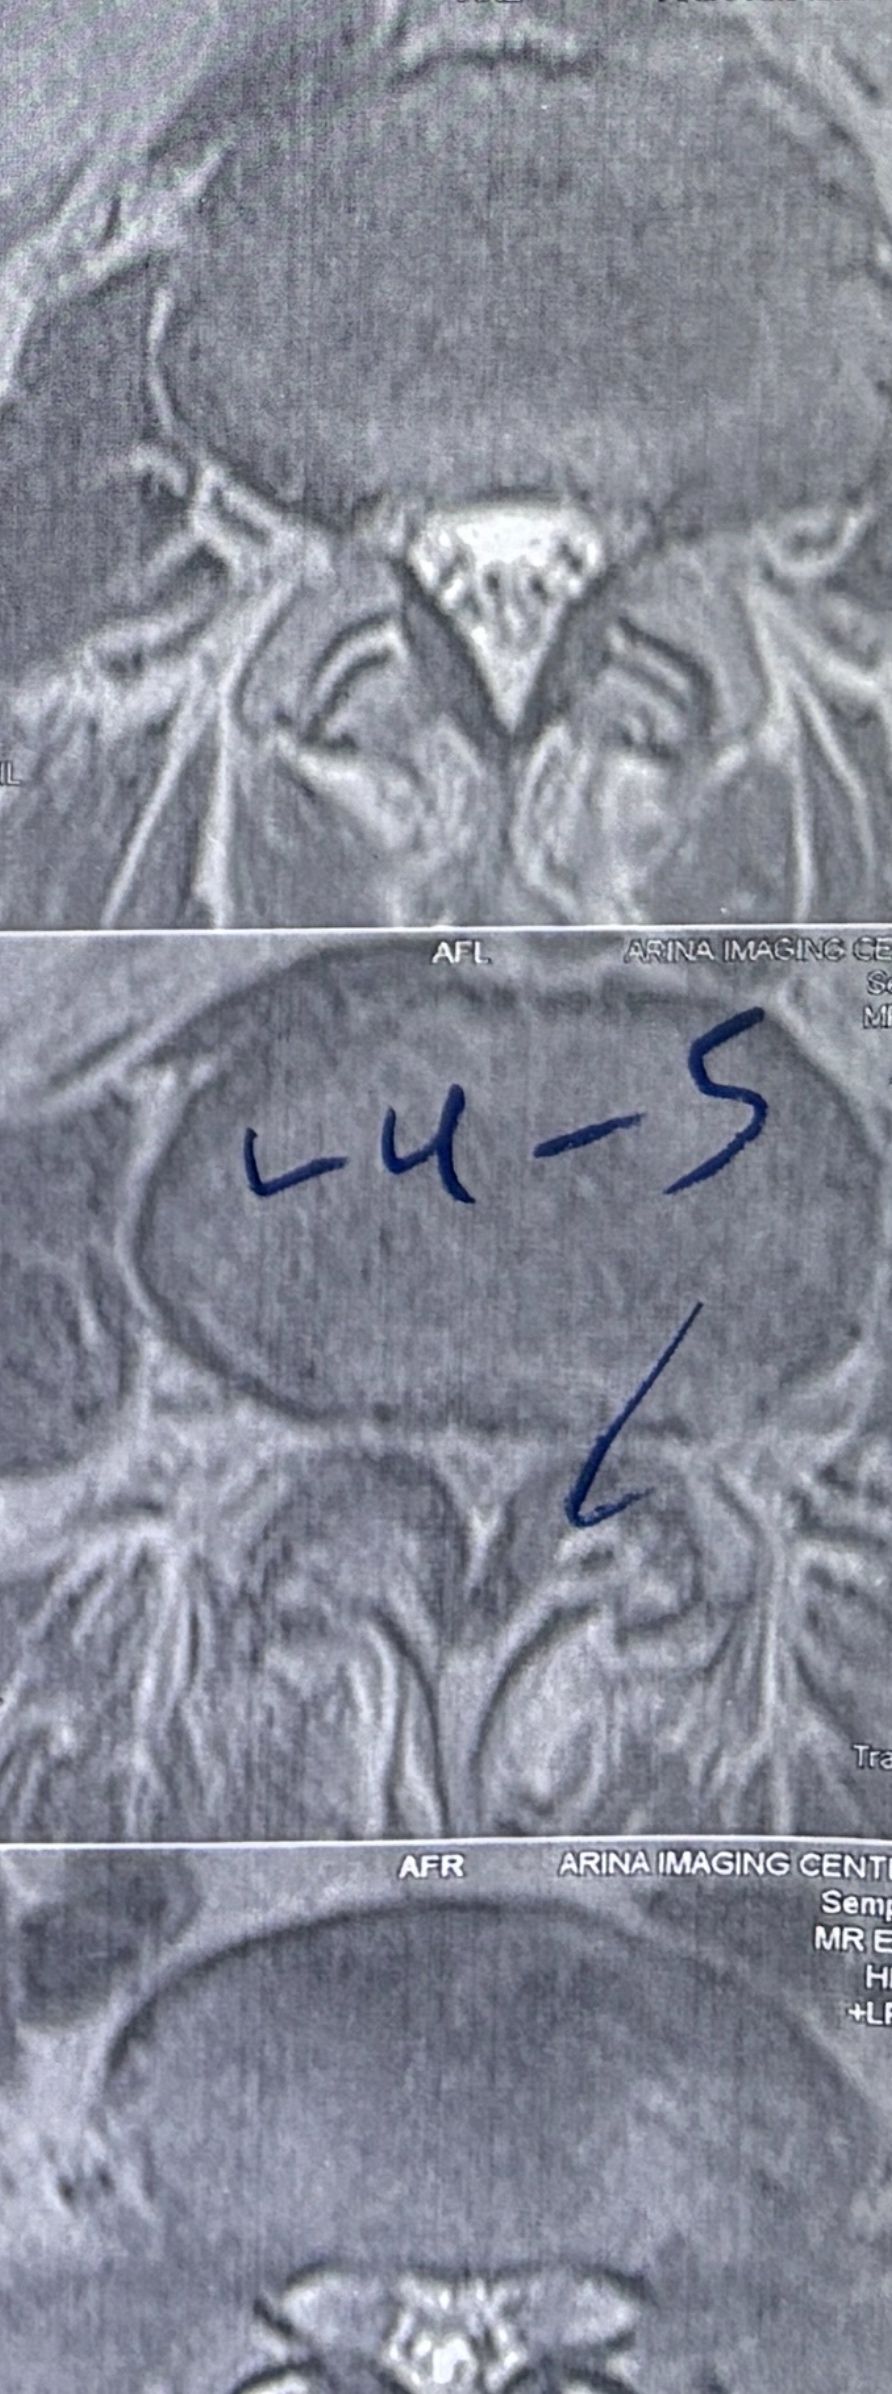

46 years old female patient presented to my clinic yesterday june 1/2025 with LBP and radicular L leg pain for several months which hasn’t responded to physio 2 neurosurgeons have visited her and didn’t suggest any surgery Neurological exam was unremarkable please see her mri/ emg/ncv and her huge tarlov cyst and possible L IVF L4-5 hyperbulge I ordered sacrum mri and ct scan and new emg/ncv and asked her with her sacral Ct scan and MRI first sees another two famous neurosurgeons and see if that large cyst is the reason for her pain if not i can work on her L4-S1 area Do you think her radicular pain can originate from her large cyst in sacrum? Do you consider surgery and removing her sacral cyst?

L4-L5 level:

sever L4-5 canal stenosis mainly due to FL hypertrophy?

CSF block. Mild L3 retrolisthesis, facets hypertrophy bilateraly causing L and R IVF stenosis, disc hyperbule